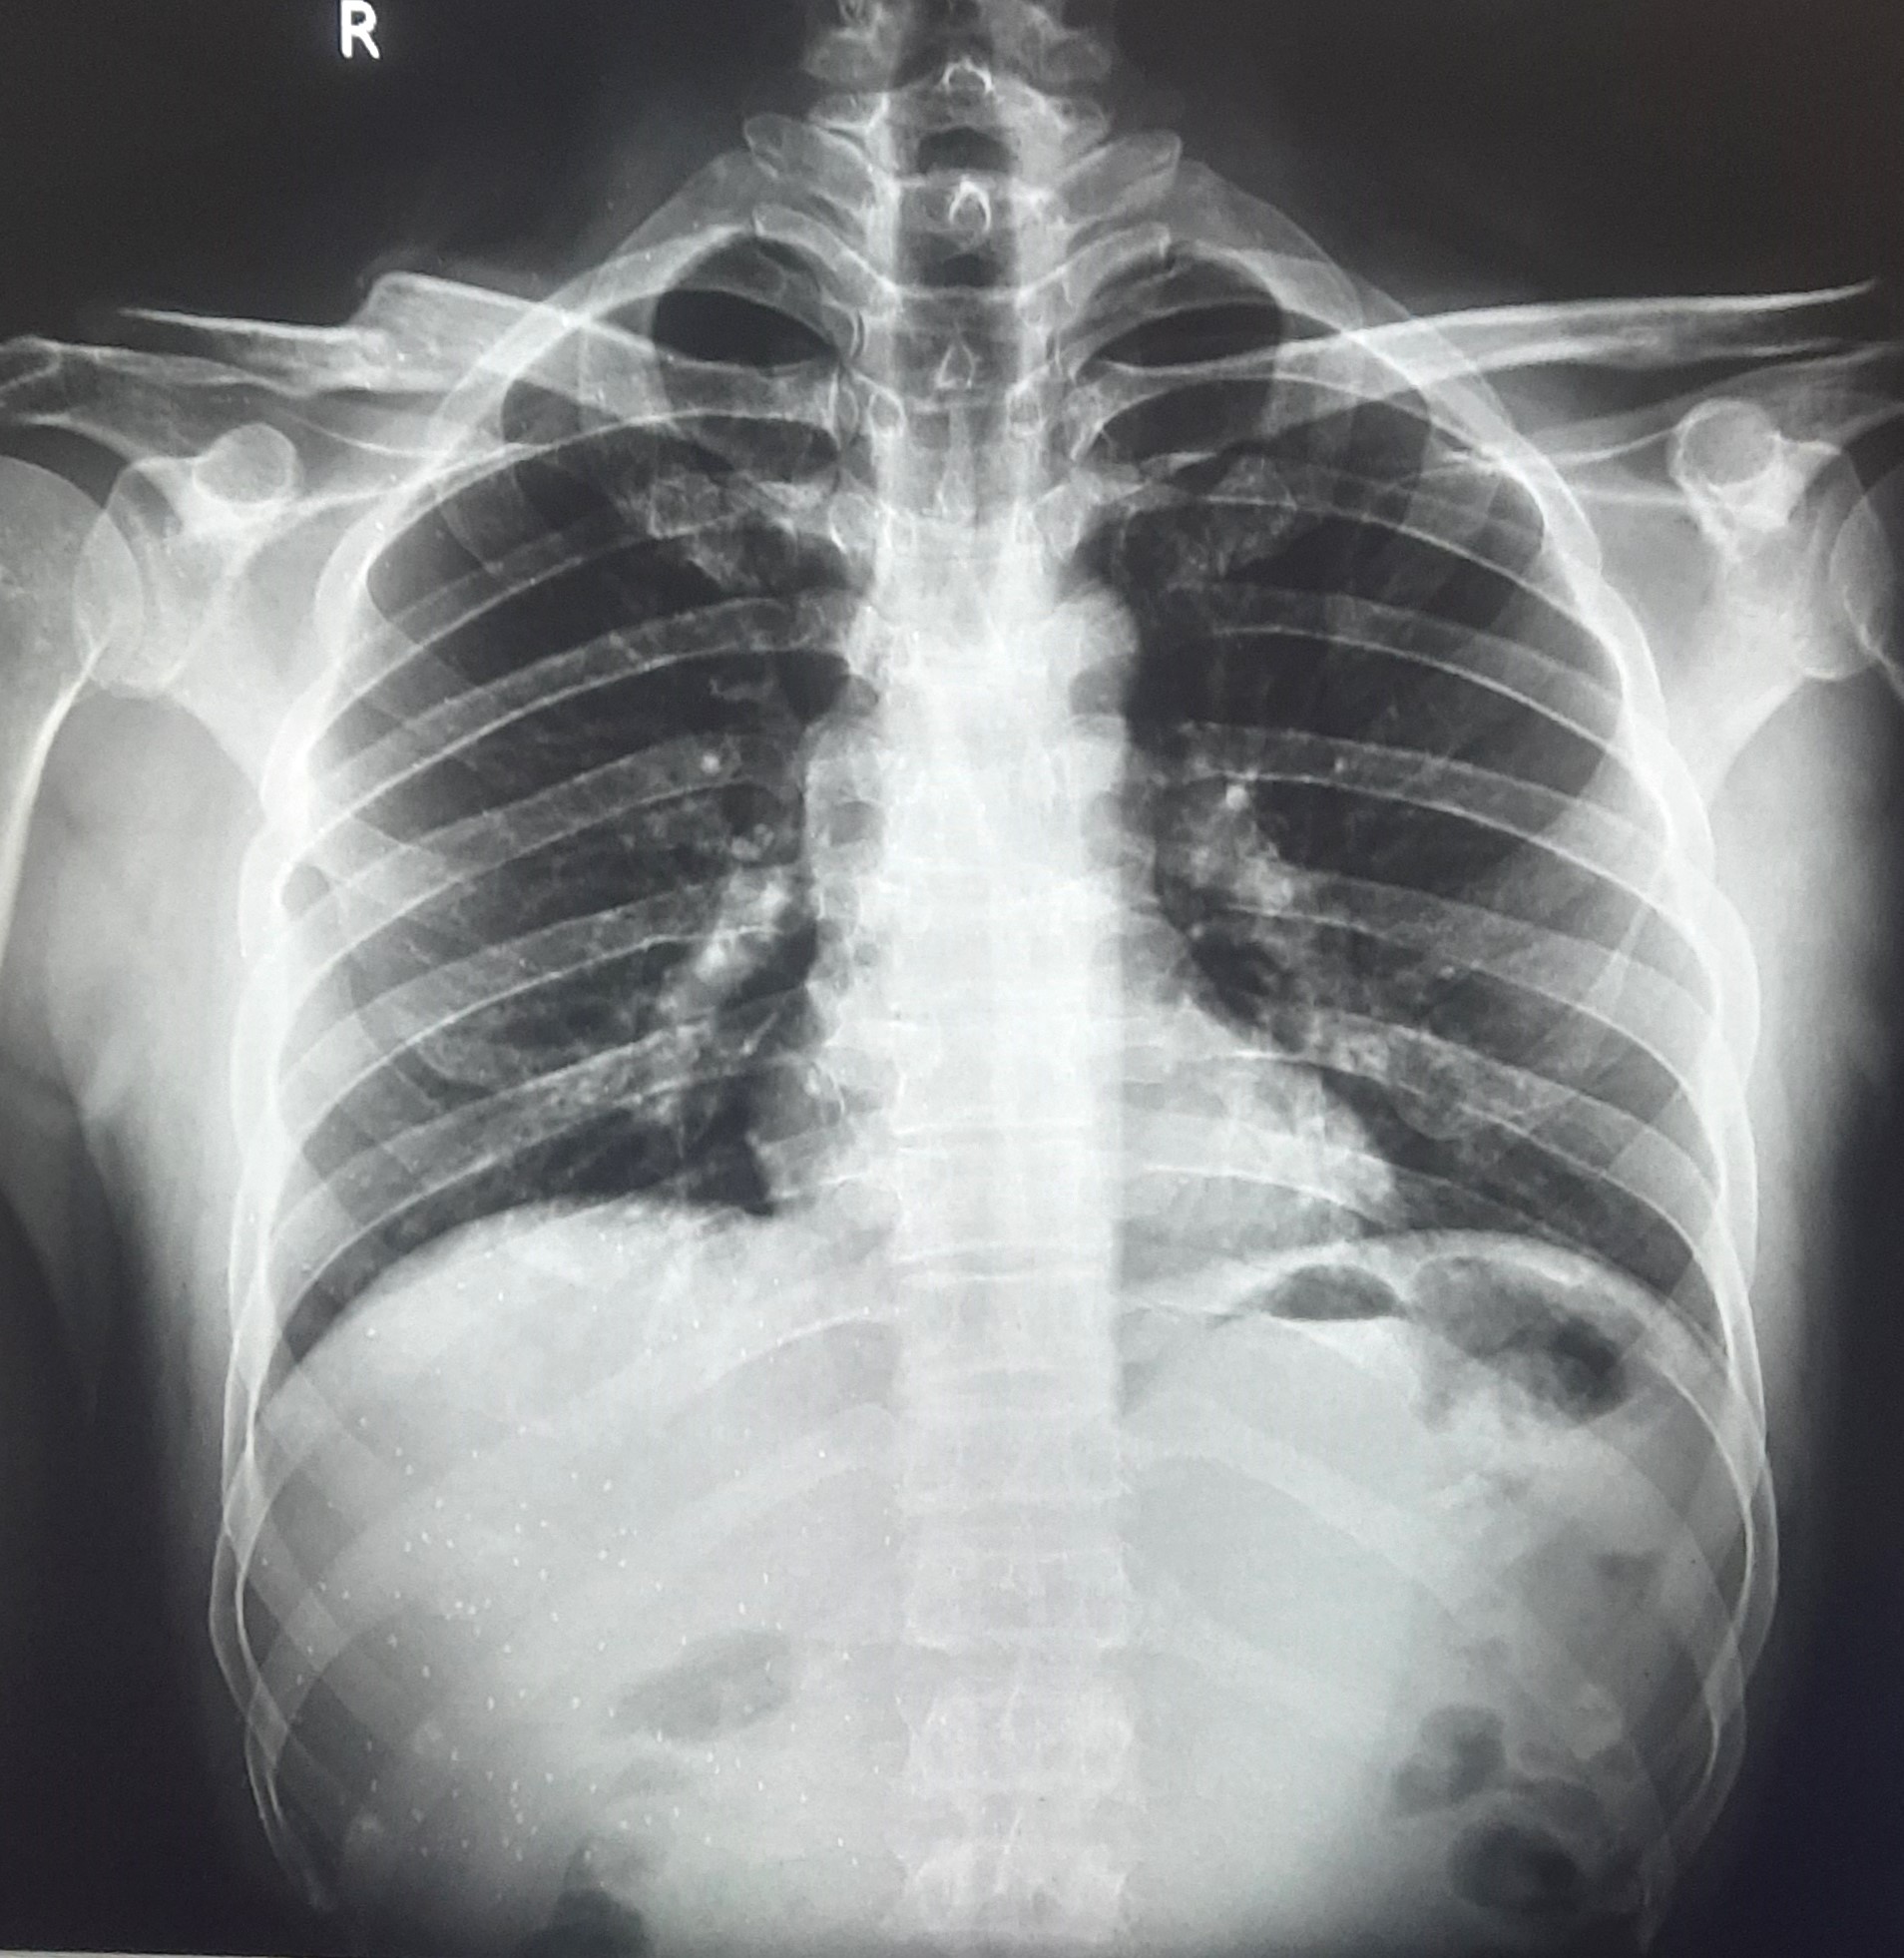

| 220 | IGGMC, Nagpur, Nagpur | P2 | 29-4252 | AMOL PAUNIKAR | Consent taken on Paper | 36 Yrs. |

Provisional Diag : BILATERAL INFILTRATION ? MILLIARY TB

Final Diag : MILLIARY TB |

TB Case (Confirmed) | MILLIARY TB | Abnormality visible on x-ray |

View |